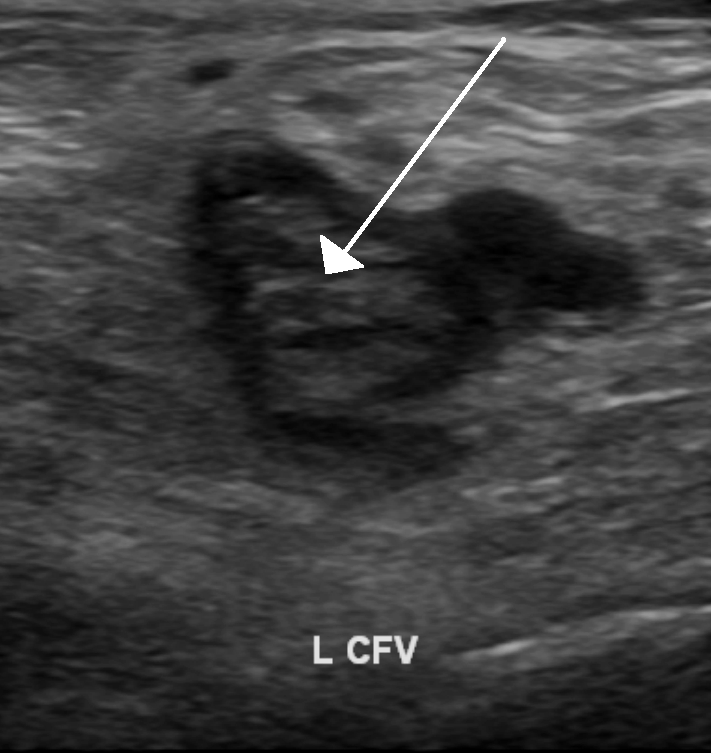

압박 심부정맥 혈전증 의심 환자에 대한 초음파 검사는 표준 진단 방법이며 초기 심부정맥 혈전증을 감지하는 데 매우 민감하다.[100] 압박 초음파 검사는 일반적으로 압축 가능한 정맥의 벽이 가벼운 압력에서 붕괴되지 않을 때 양성으로 간주된다.[22]

심부정맥 혈전증 의심 환자에 대한 초음파 검사는 표준 진단 방법이며 초기 DVT를 감지하는 데 매우 민감하다.[100] 압박 초음파 검사는 일반적으로 압축 가능한 정맥의 벽이 가벼운 압력에서 붕괴되지 않을 때 양성으로 간주된다.[22] 혈전 시각화가 때때로 가능하지만, 필수는 아니다.[99] 3가지 압박 초음파 검사 기술을 사용할 수 있으며, 3가지 방법 중 2가지 방법은 며칠 후에 두 번째 초음파 검사를 통해 진단을 배제해야 한다.[100] 전체 다리 초음파 검사는 반복적인 초음파 검사가 필요하지 않은 옵션이다.[100] 이중 및 컬러 도플러 초음파 검사를 포함한 초음파 방법은 혈전을 추가로 특징지을 수 있으며,[101] 도플러 초음파 검사는 압축 불가능한 장골 정맥에서 특히 유용하다.[99]